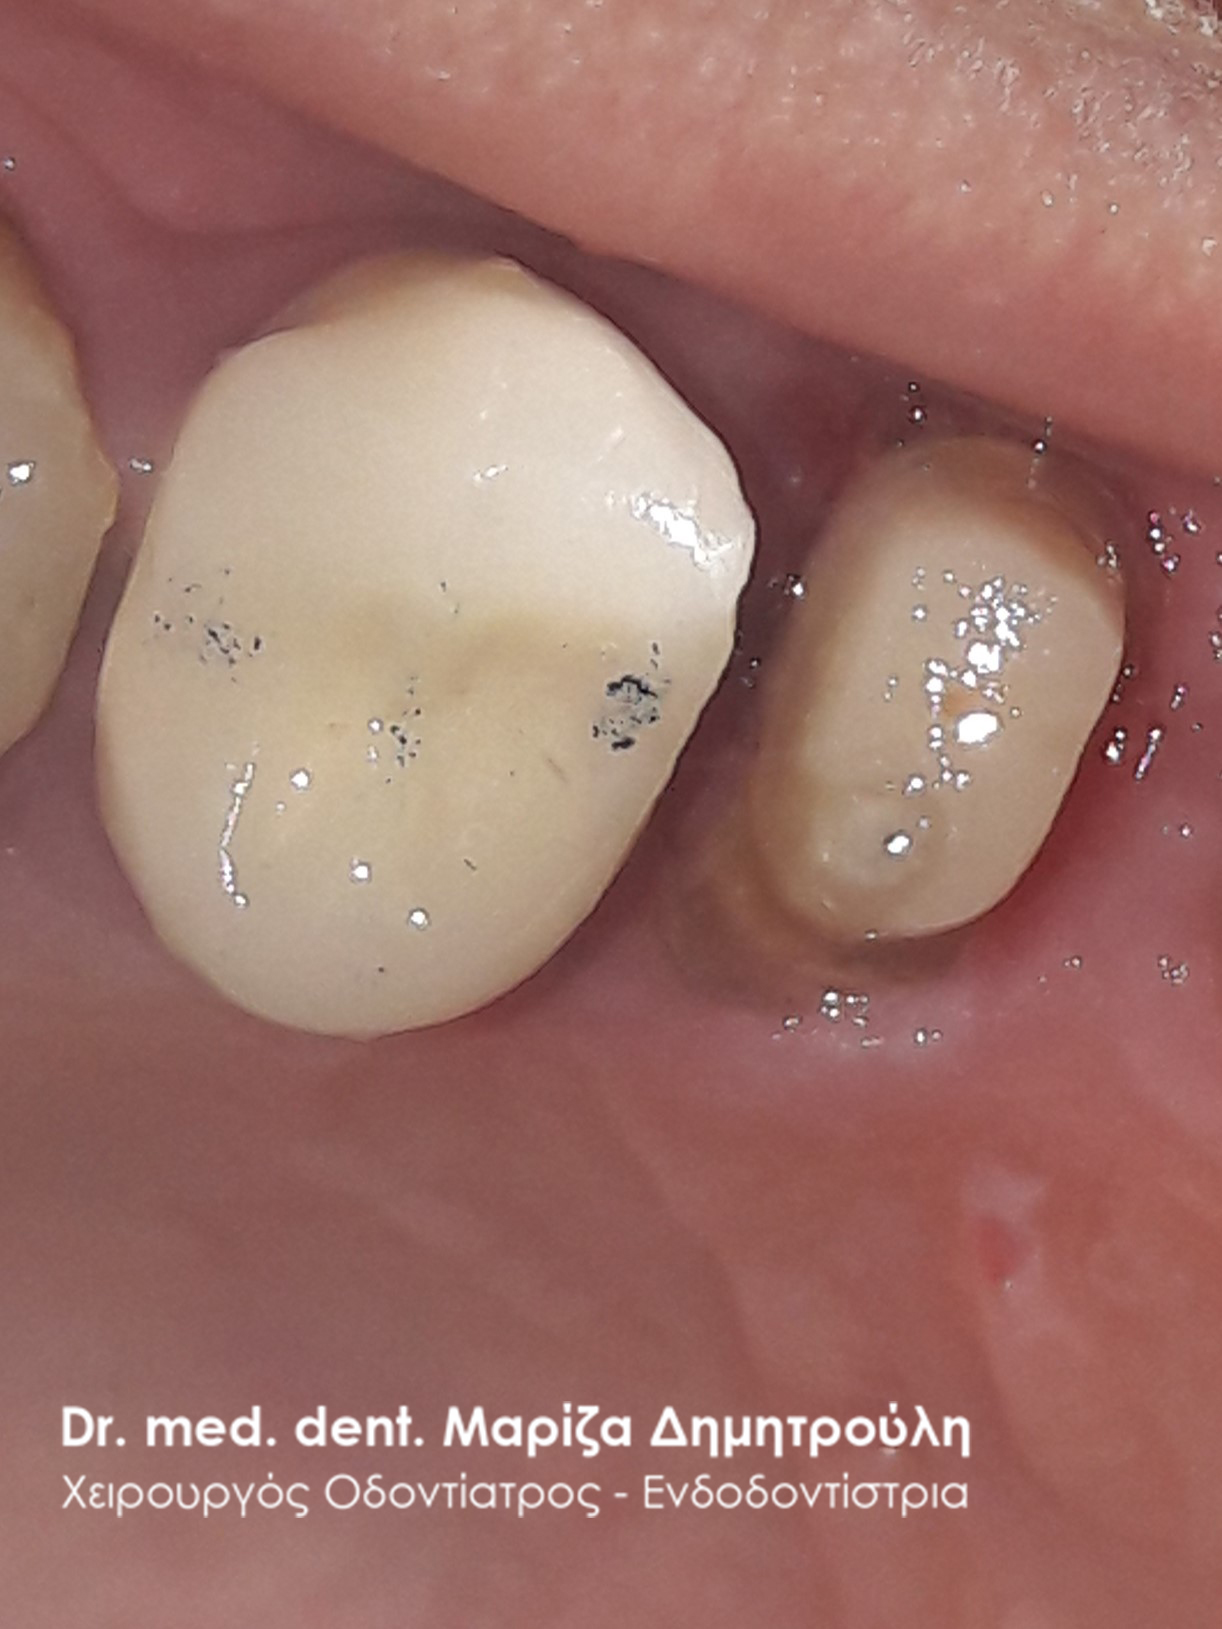

Περιστατικό – Ολοκεραμική στεφάνη / θήκη ζιρκονίου στον άνω αριστερό γομφίο

Η ασθενής επισκέφτηκε το ιατρείο μας γιατί πονούσε στον πρώτο άνω αριστερό γομφίο. Η κλινική και ακτινογραφική εξέταση φανέρωσε την αναγκαιότητα απονεύρωσης του δοντιού. Μετά το πέρας της ενδοδοντικής θεραπείας και εφόσον το οδοντικό έλλειμα ήταν μεγάλο, κρίθηκε απαραίτητη η προστασία του απονευρωμένου δοντιού με ολοκεραμική θήκη.

Αρχική κλινική εικόνα του δοντιού με το προσωρινό σφράγισμα απονεύρωσης

Τελική κλινική εικόνα με την ολοκεραμική θήκη δοντιού